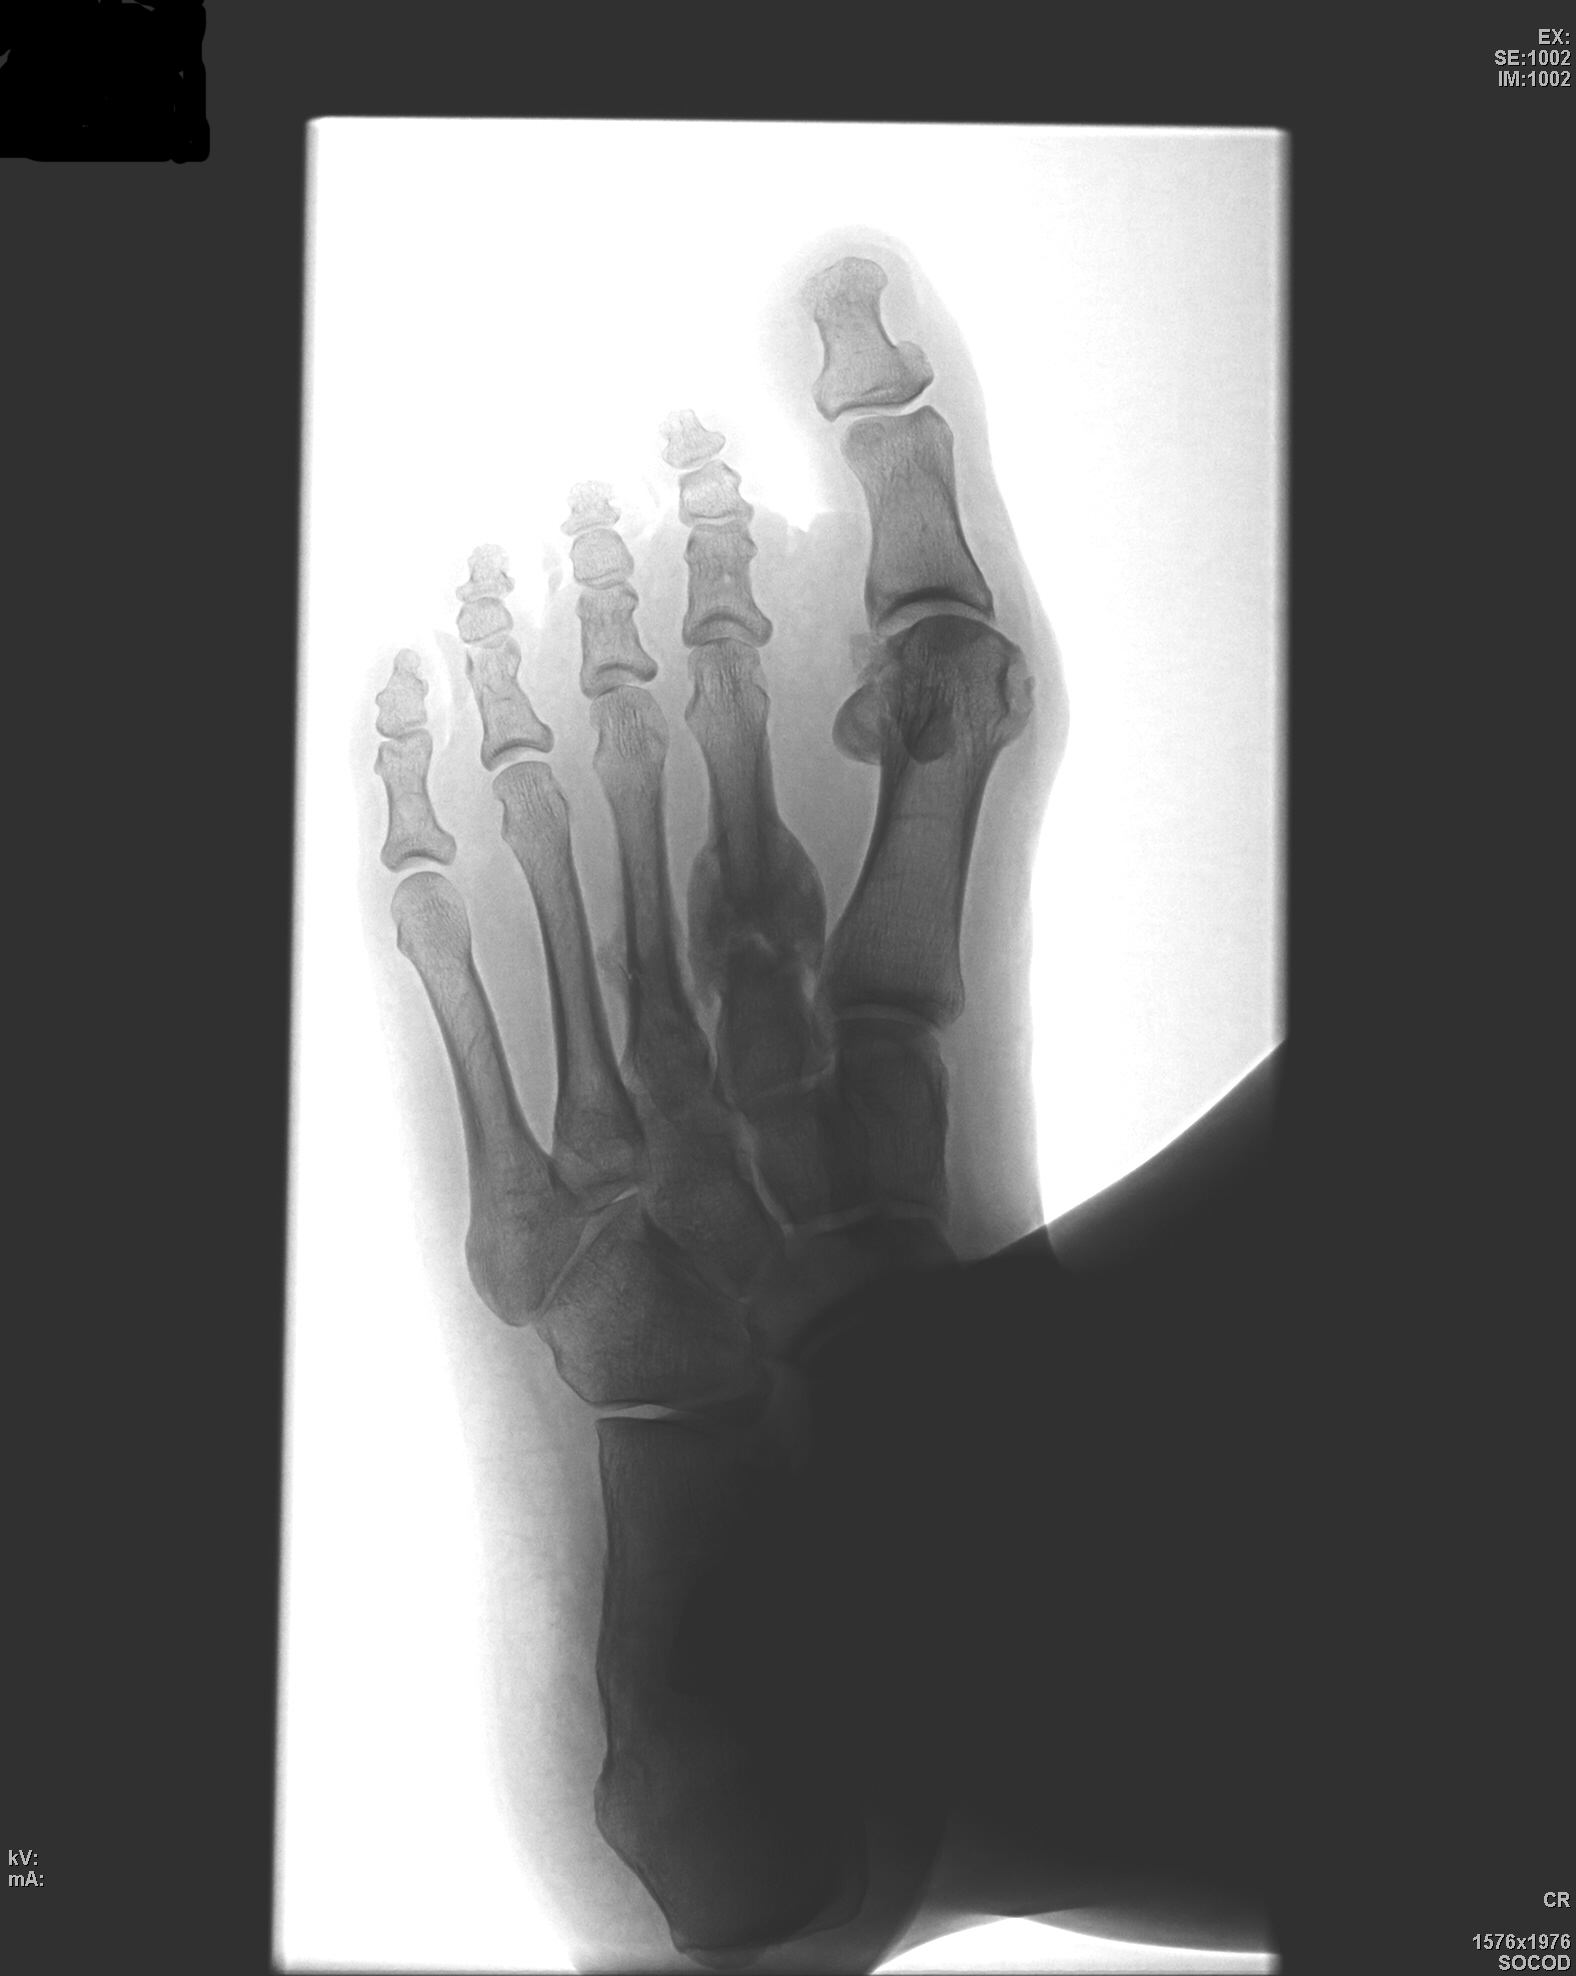

Пациентка часто ходит на высоких каблуках.Недавно появились слабо выраженные боли в левой стопе,обратилась к хирургу,который направил на рентгенографию.

Мне кажется что структурная перестройка 2й плюсневой кости характерна для данной болезни.

1. Четко определяются линии переломов в проксимальных отделах 2 и 3 плюсневых костей. Эти линии переломов помечены желтыми стрелками.

2. Избыточная костная мозоль в области 2 плюсневой кости обусловлена отсутствием "фиксации отломков", периостальная реакция, также имеет место быть и в области 3 плюсневой кости - красные стрелки.

рентгенологически можно и подуматьо травме.Однако пациентка бесспорно говорит "нет".Она даже была " в шоке"когда узнала, что у нее перелом,ведь она чуть ли не в припрыжку пришла на исследование.спасибо за комментарии, грамотно.

Травма была однозначно, об этом даже и не стоит спорить, и об этом свидетельствуют следующие признаки:

И самый коронный признак. Зеленые стрелки показывают место, откуда "откололся" фрагмент костной ткани, помеченный сиреневой стрелкой - головка 1 плюсневой кости.

Не могу согласиться с Вами, Валентин Львович. Здесь все характерные признаки болезни Дойчлендера II-III плюсневых костей, причем на разных стадиях